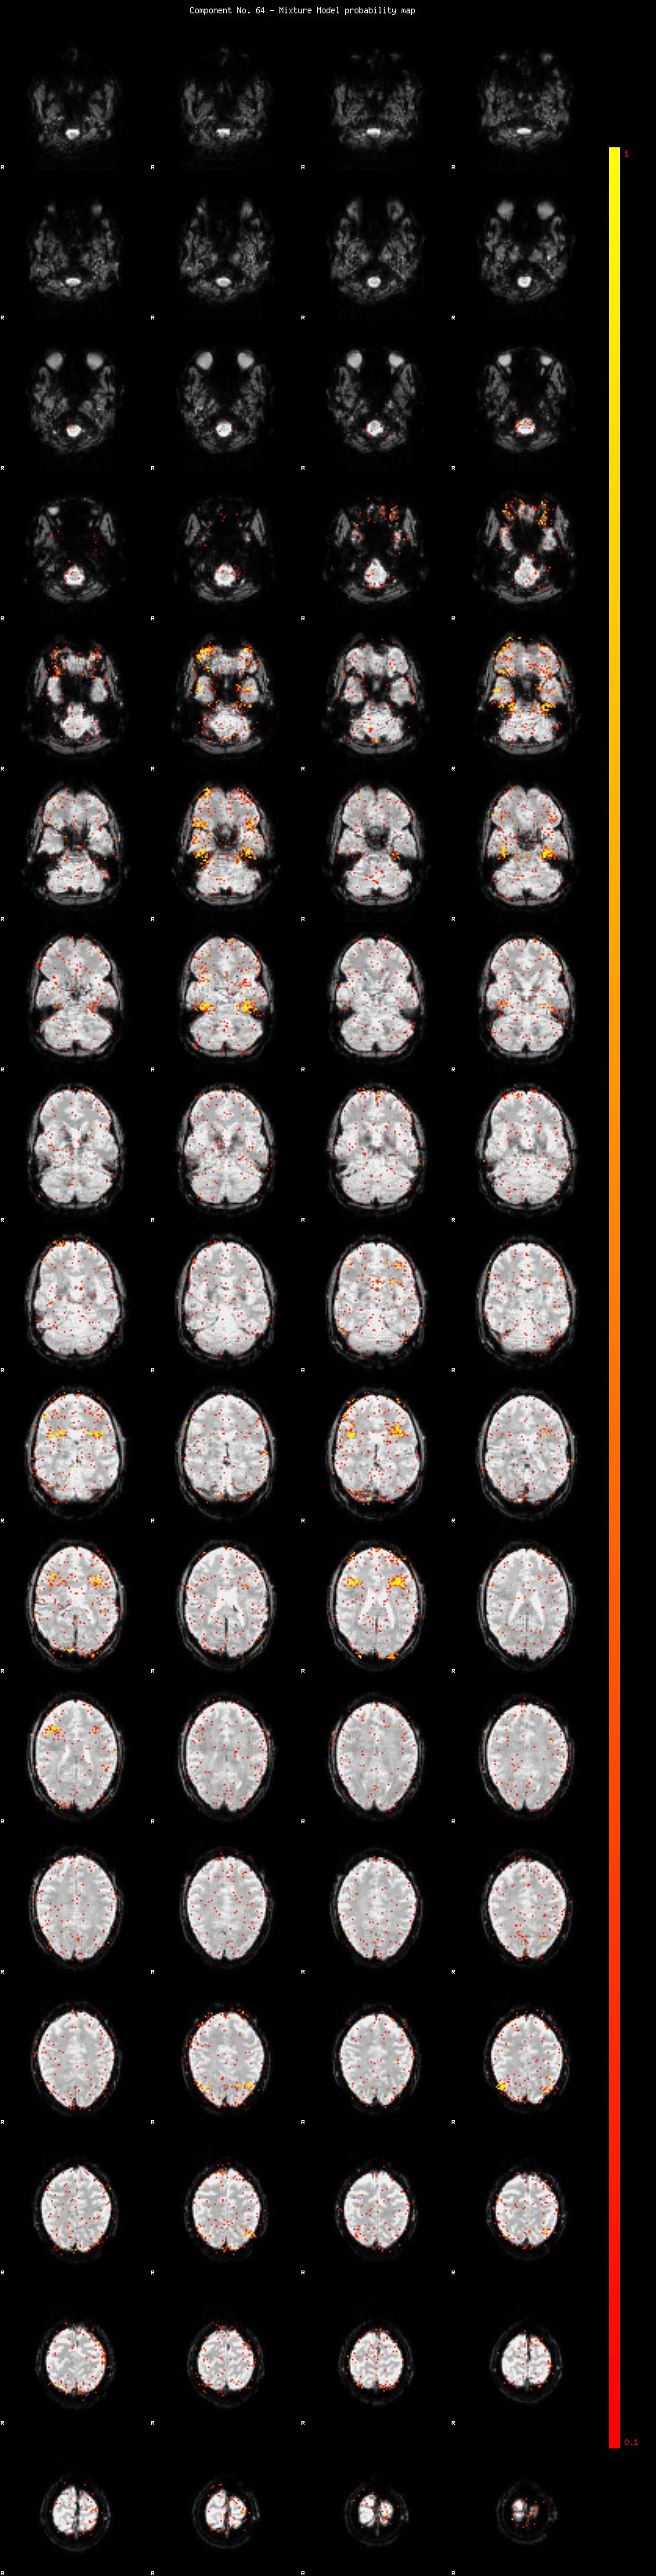

IC_64 Mixture Model fit

Means : -0.000000 2.393580 -2.228003

Vars : 1.000000 1.828110 1.341076

Prop. : 0.972583 0.014472 0.012946